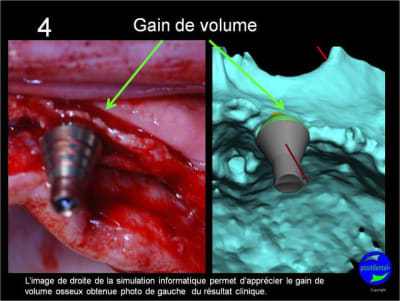

votre avis sur ce cas clinique

Pose d’un implant au maxillaire dans une zone de faible densité

Léger summers

précision de la chirurgie guidée condensée